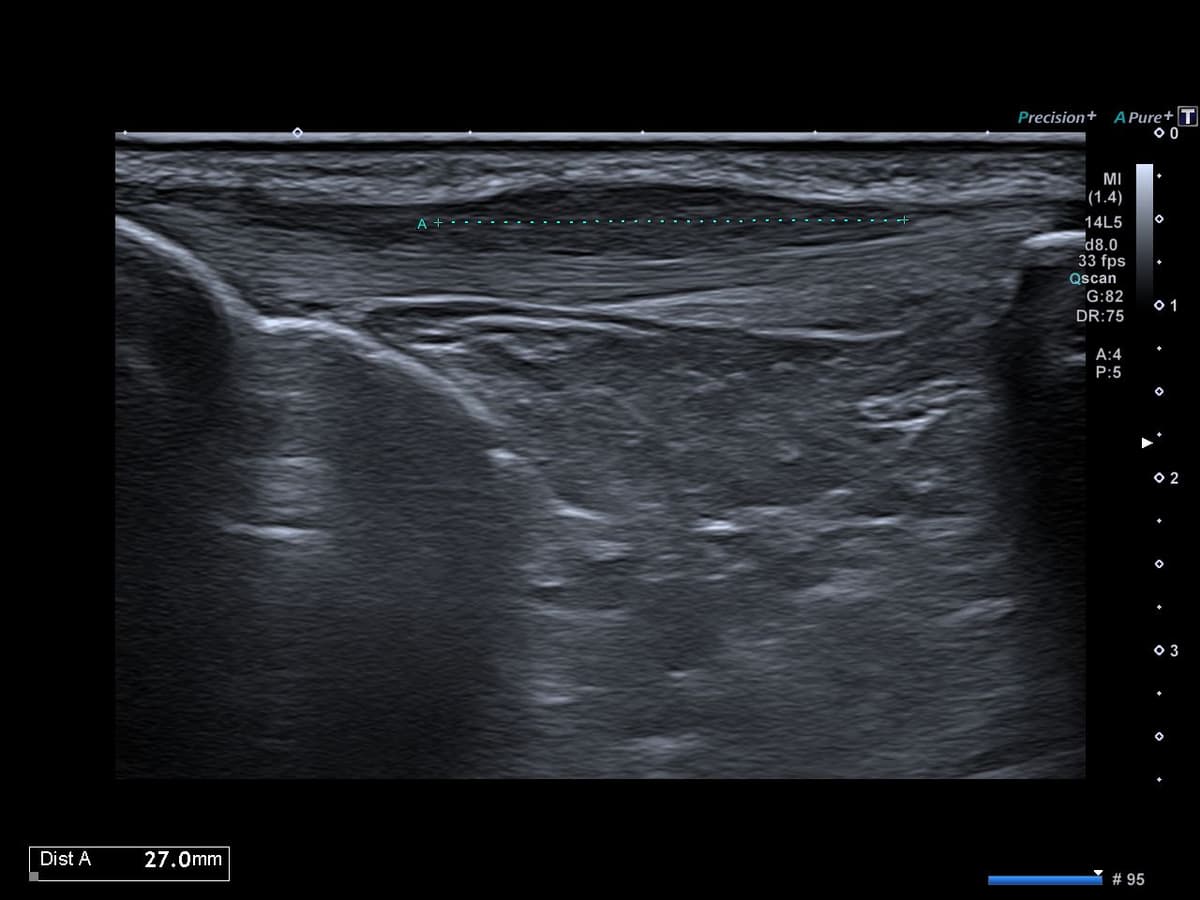

Gonalgie antérieure post traumatique traînante sans notion de pratique de sport de saut.

US